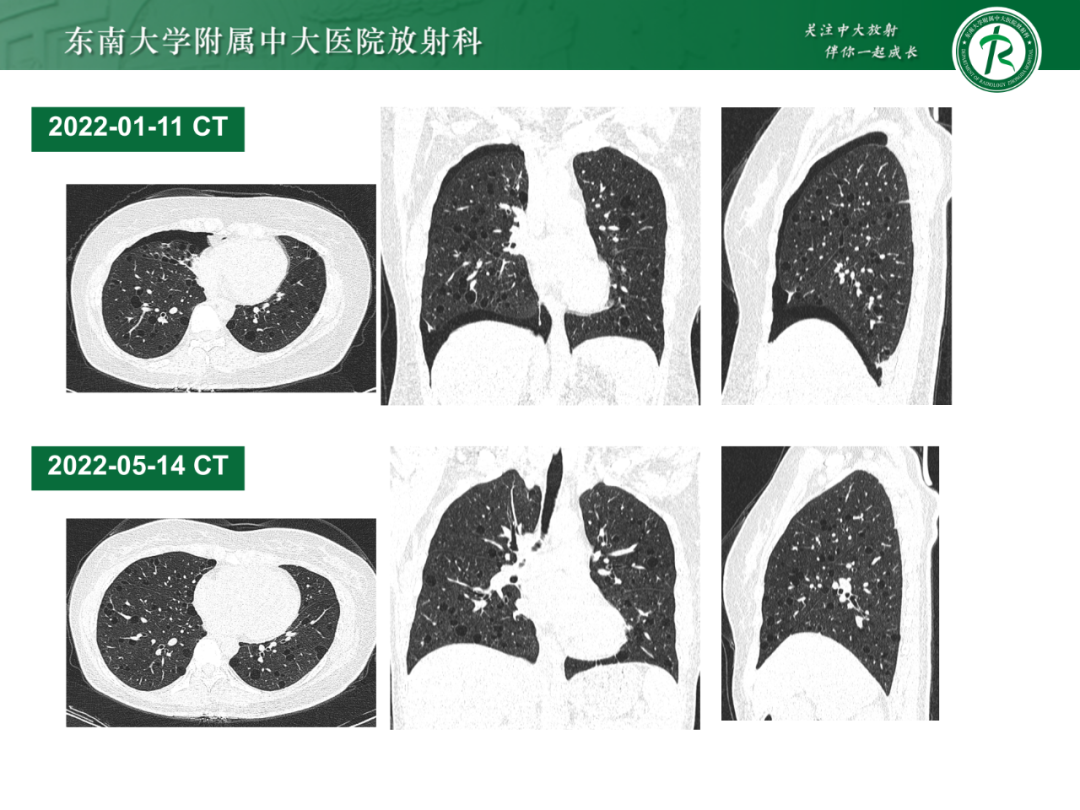

图片来源 东南大学附属中大医院放射科